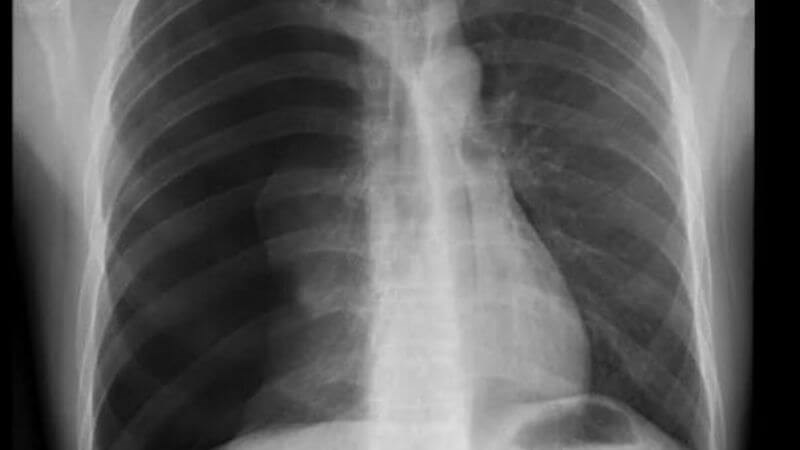

- X-quang ngực: đây là phương pháp sử dụng tia X để thu được hình ảnh của phổi nhằm xác định có xuất hiện xơ nang hay giãn phế quản hay không.

X-quang giúp xác định cấu trúc nang bất thường ở phổi